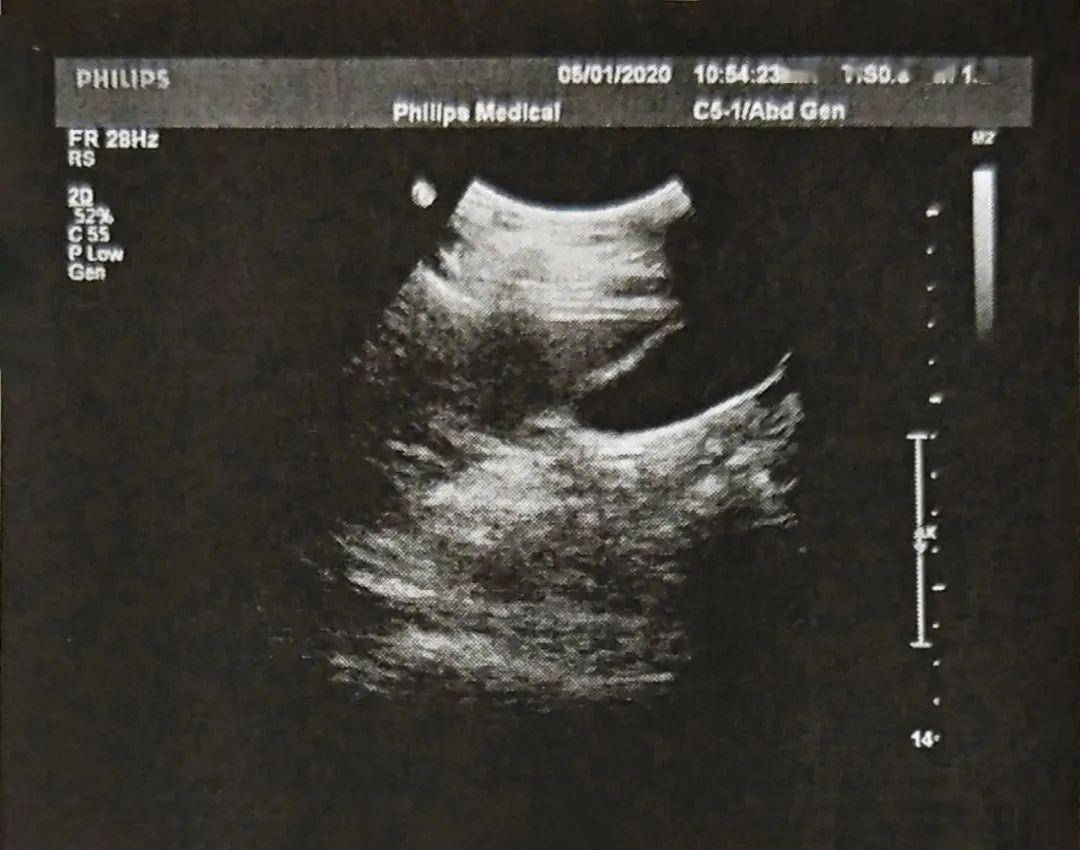

镜面右位心的超声模板

镜面右位心的超声模板,镜面右位心报告书写

镜像右位心,永存右上腔静脉

镜面右位心报告书写

右位心的超声模板

镜面右位心

右位心超声报告模板